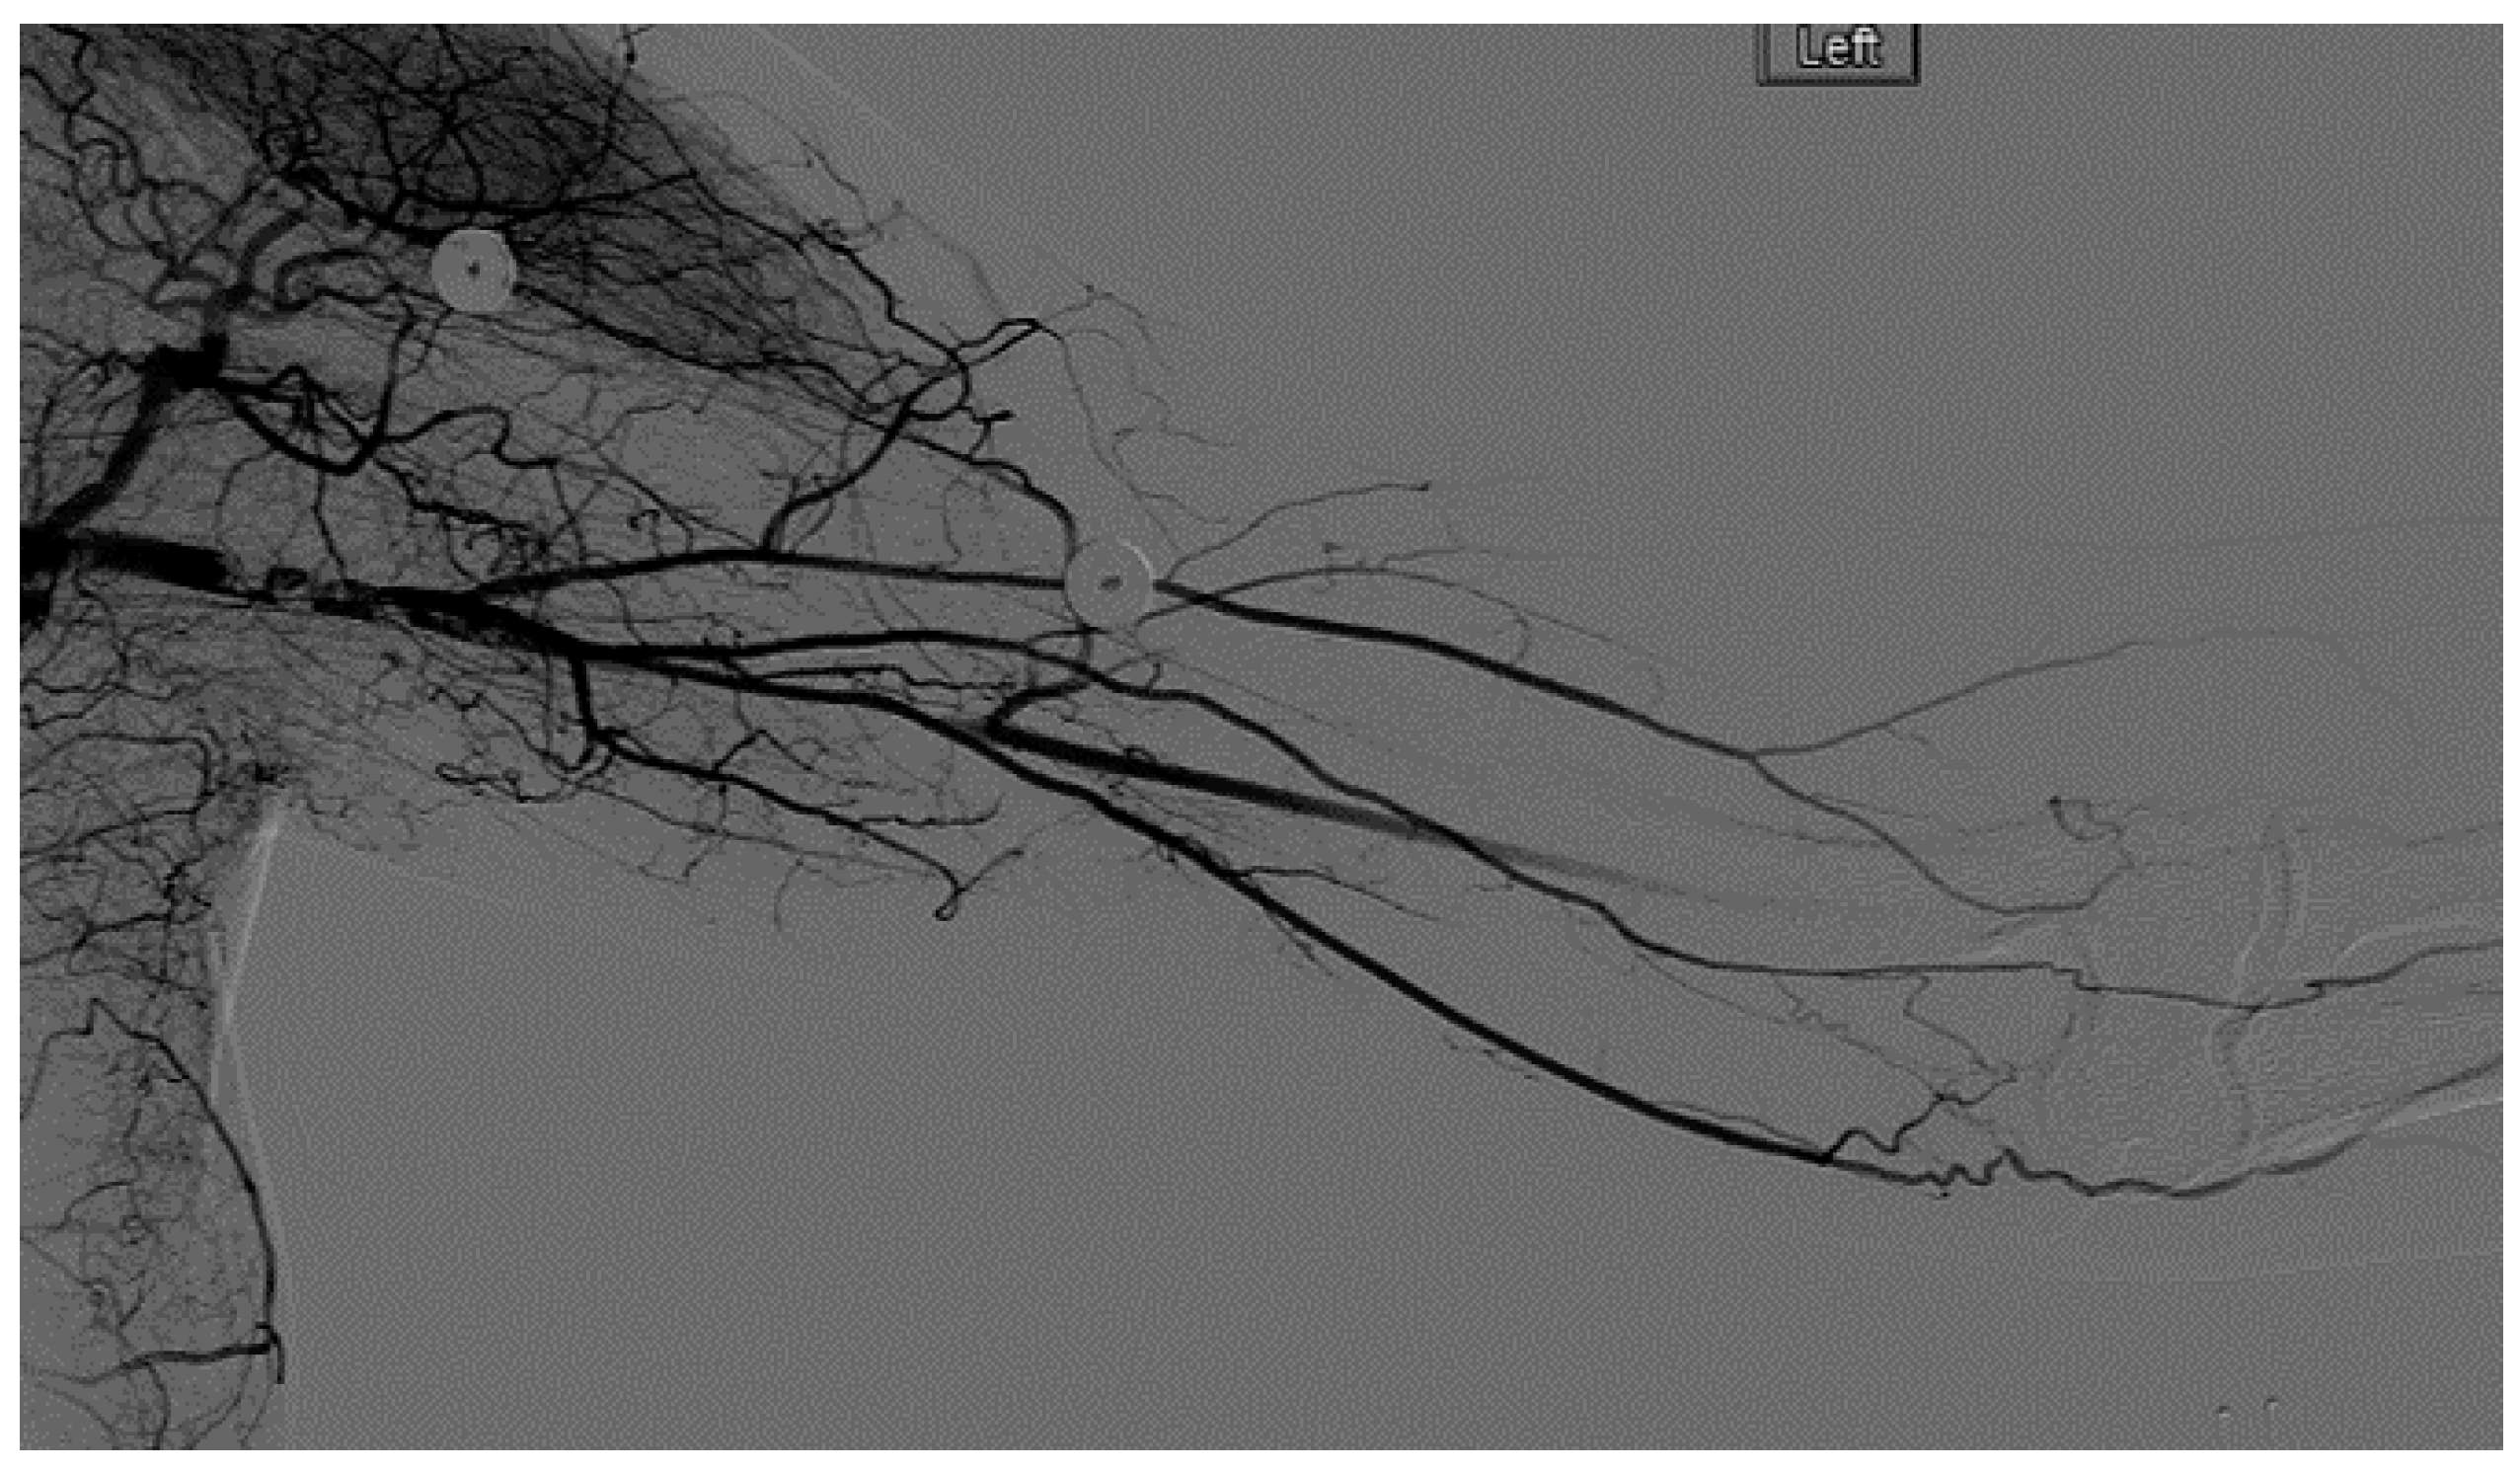

A heparin drip was then initiated, and she was taken to the catheterization lab for thrombolysis. This was carried out with Alteplase for 48 h as the patient had strong collaterals and was not in limb-threat (Figure 7, Figure 8, Figure 9, Figure 10 and Figure 11). However, her radial artery remained occluded. She was then taken to the operating room for thromboembolectomy of the left brachial and radial arteries (Figure 12). She was continued on anticoagulation post-operatively and was discharged.

Figure 9.

Distal left arm angiography in an ATOS patient demonstrating an occluded radial artery at the origin and ulnar artery at the mid-forearm.

Figure 10.

Angiography of the radial and ulnar arteries as well as the palmar arch and digital branches in an ATOS patient with a brachial thrombus.

Figure 11.

Distal brachial artery thrombosis in an ATOS patient.